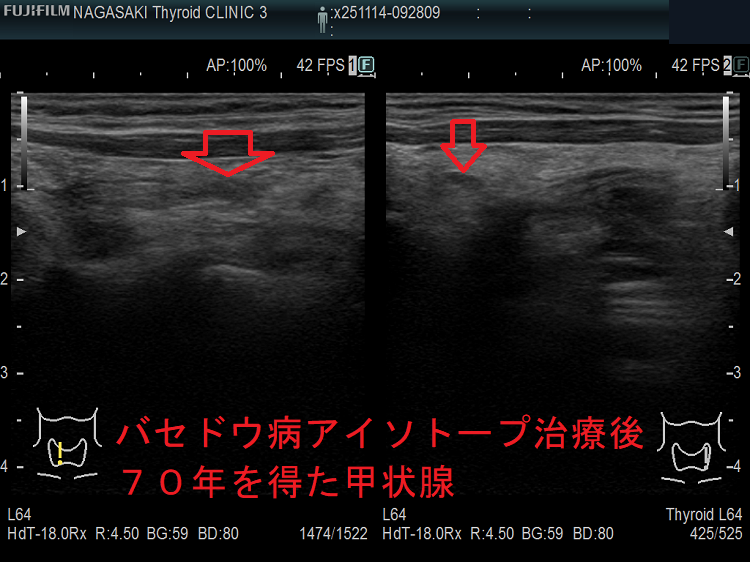

バセドウ病/甲状腺機能亢進症のアイソトープ(放射性ヨウ素; I-131)治療後の管理・ホルモン補充療法[橋本病 バセドウ病 長崎甲状腺クリニック 大阪]

数年で放射線治療後甲状腺機能低下症になり、甲状腺ホルモン剤[チラーヂンS錠(レボチロキシン ナトリウム)]の服薬が生涯必要になります。しかし、

新たに提唱された「甲状腺機能正常を目指した治療目標」のため、中途半端な量あるいは少量のアイソトープ(放射性ヨウ素; I-131)を使用した場合、甲状腺機能亢進症が再発するのは当然と思います(新しく提唱された治療目標)。筆者に言わせれば、甲状腺機能亢進症/バセドウ病を甘く見過ぎています。

一方、アイソトープ(放射性ヨウ素; I-131)治療が成功して、甲状腺重量が10g以下に十分縮小し、甲状腺ホルモン補充療法が必要となった後でも、稀に甲状腺中毒症状態になる場合があります。